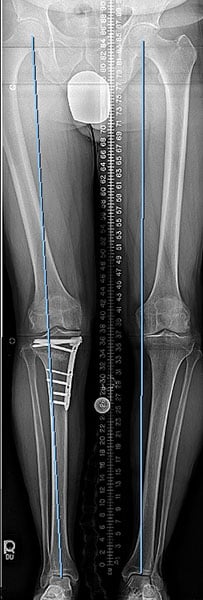

Case #74: Femur lengthening and deformity correction.